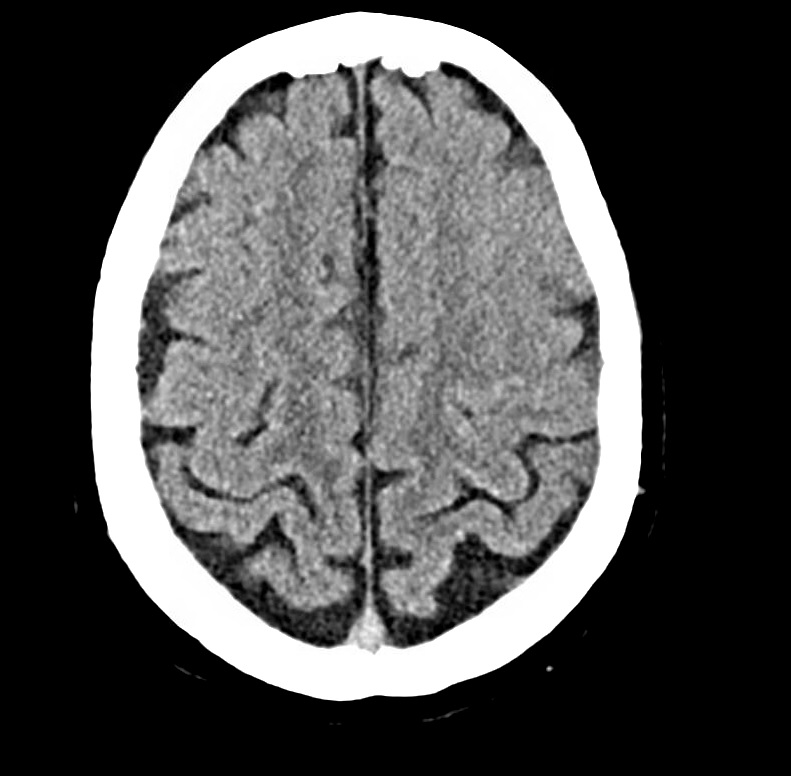

To wrap up, here’s a brain MRI showing a left MCA stroke (bright on diffusion) – based on the location, can you guess what symptoms the patient presented with?

You should be able to use to omega sign to identify this as a stroke involving the left hand knob – the patient presented with isolated right hand weakness.